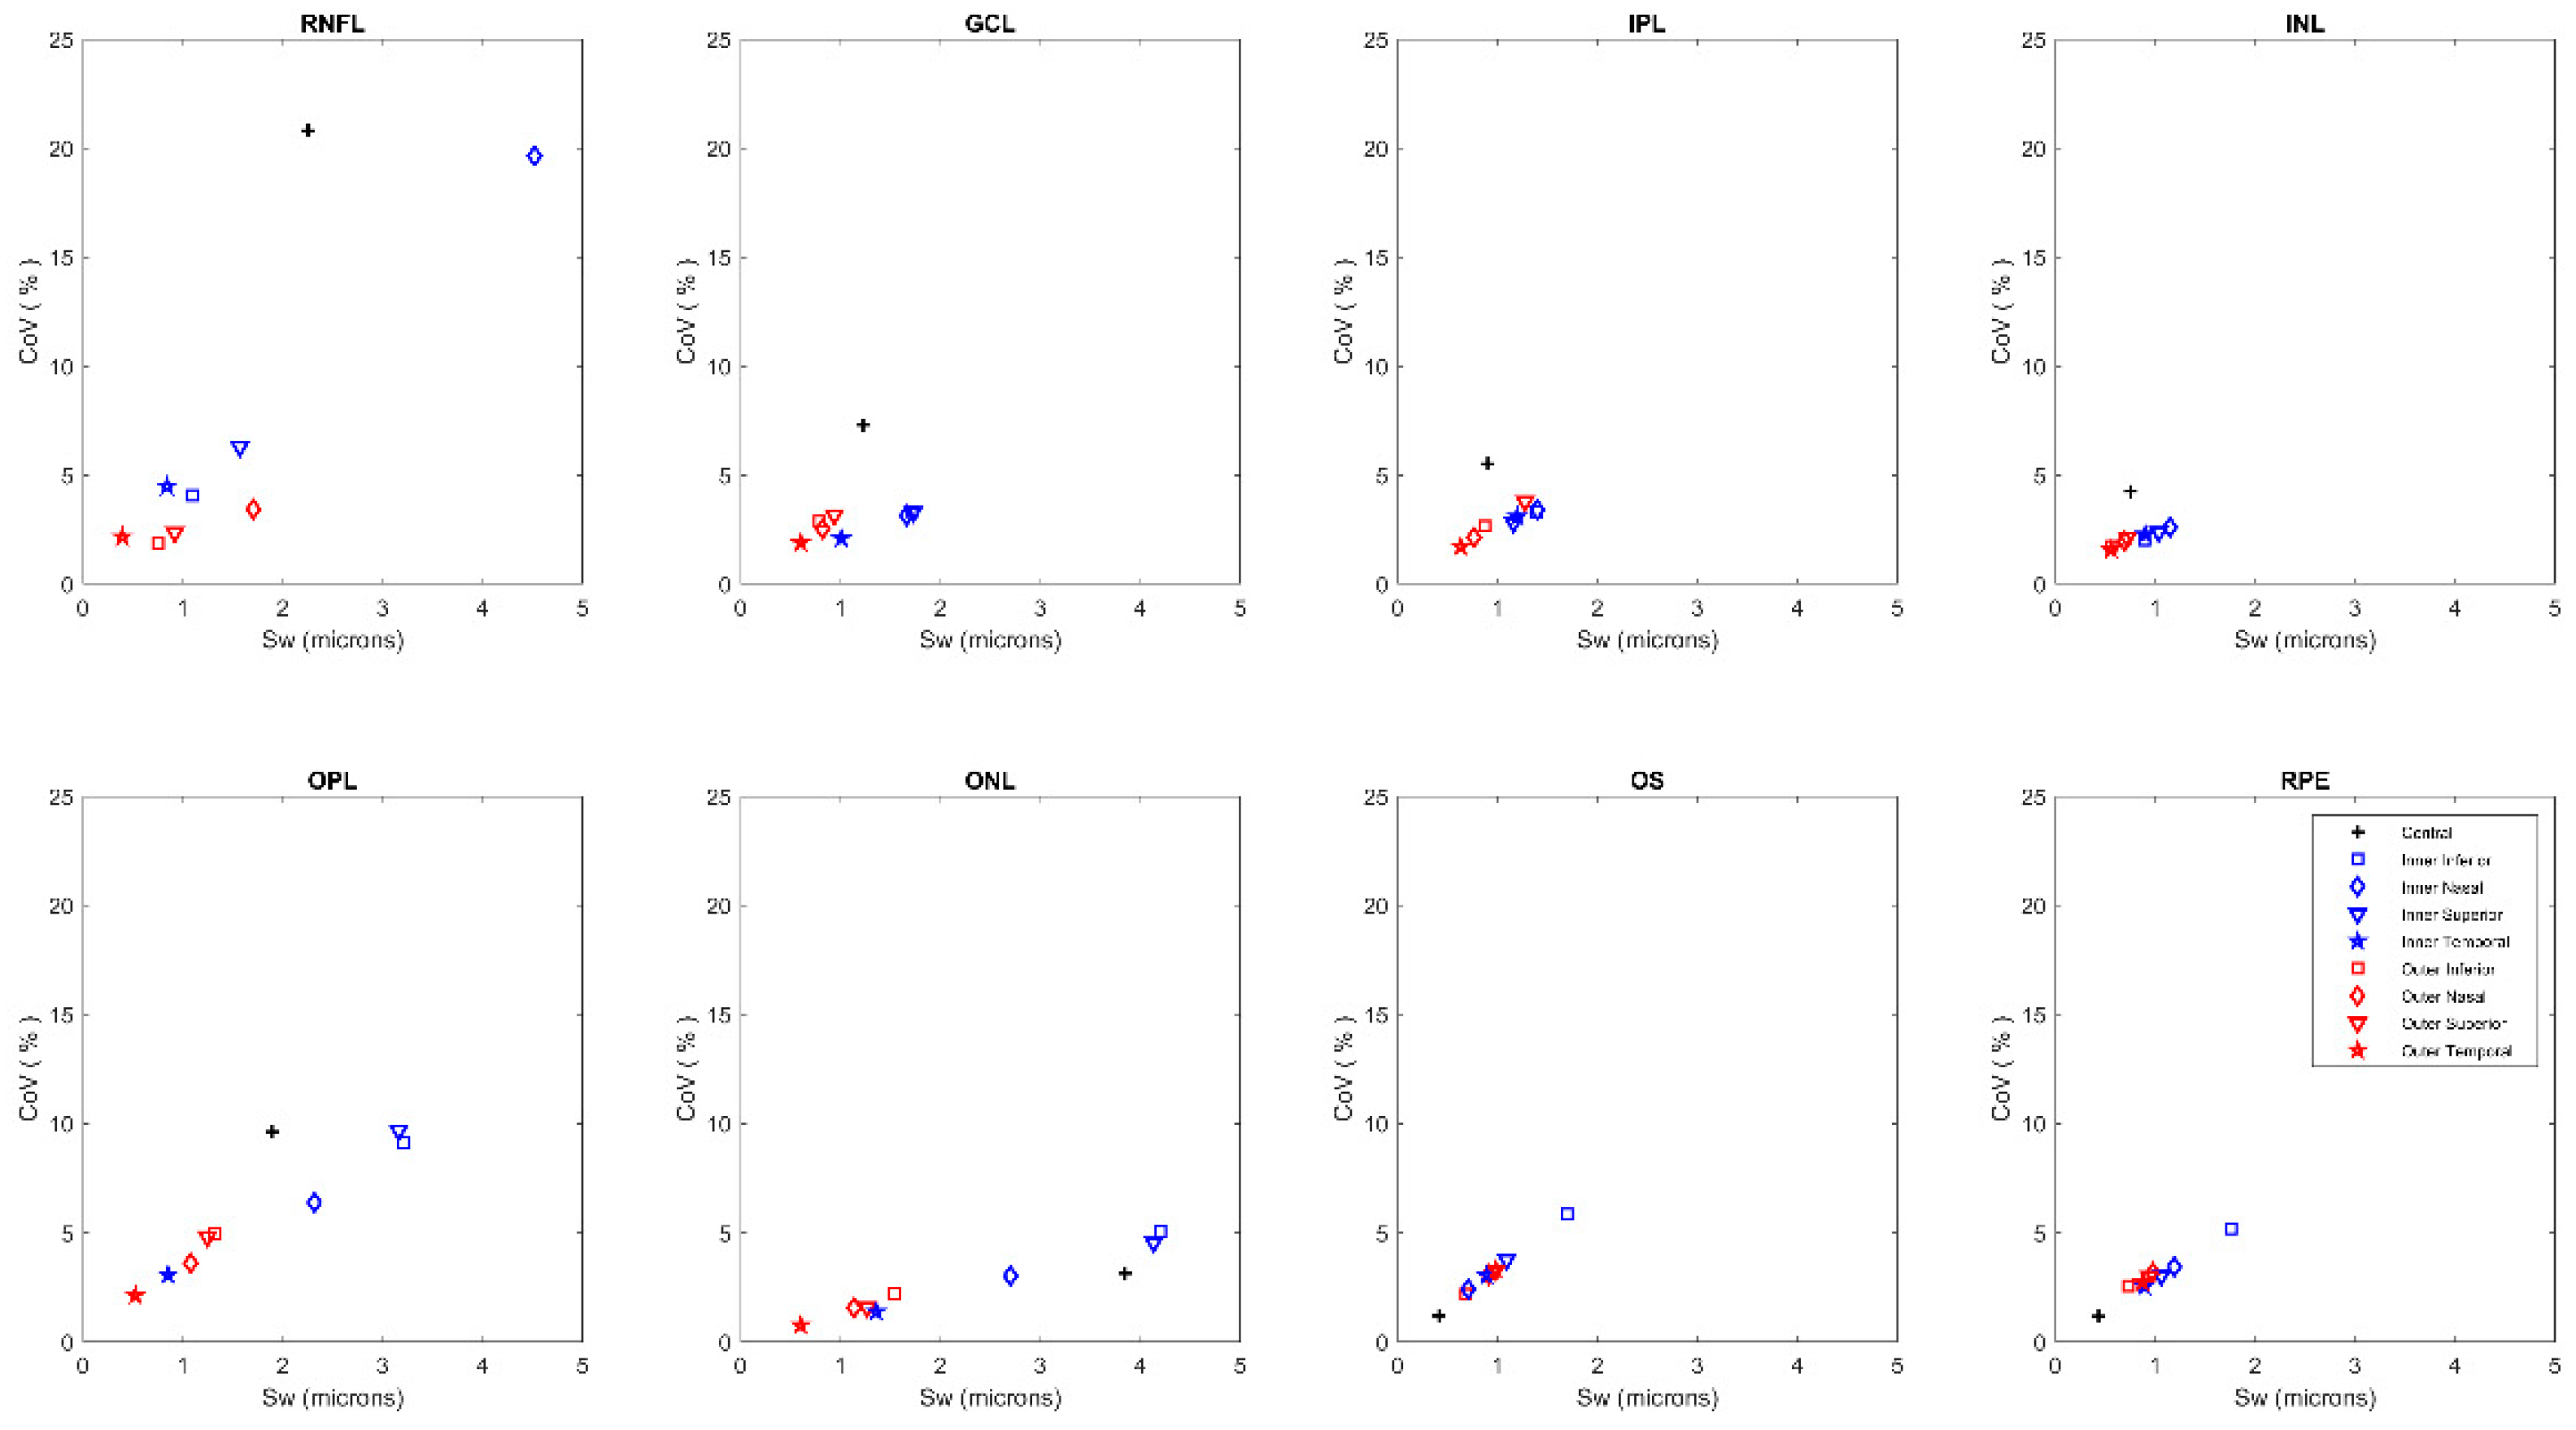

3. Results